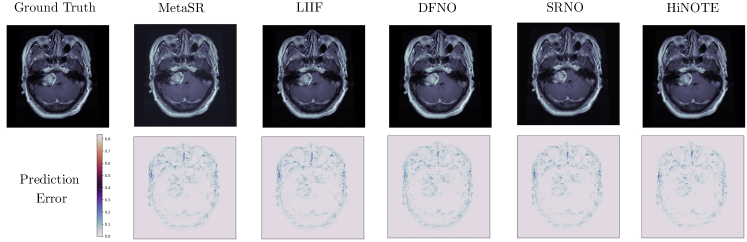

We present the test predictions of HiNOTE alongside various arbitrary-scale super-resolution baseline methods. For each figure, the super-resolved predictions are depicted in the top row, while the bottom row features error maps with respect to the reference data, with darker pixels indicating greater errors. This visual comparison not only highlights the accuracy of our model in generating high-resolution predictions but also provides a quantitative assessment of its performance by visualizing the error distribution across the domain.

Showcases. Fig.4 presents qualitative comparisons between the HiNOTE and other leading arbitrary-scale SR methods, specifically LIIF and SRNO. An expanded qualitative comparison is detailed in the Appendix B.3. The results illustrate HiNOTE’s ability to generate super-resolved images with notably sharper textures compared to these methods. For example, in the second row, which displays the absolute error between the target and the predictions, HiNOTE demonstrates superior performance to LIIF, as evidenced by the significantly lower error margins. Against SRNO, the previously best-performing arbitrary-scale SR method, HiNOTE shows marked improvements, especially noticeable in the errors pertaining to ocean areas in the images. This enhanced performance further substantiates the effectiveness of HiNOTE’s hierarchical structure in accurately modeling multi-scale data, such as climate-related imagery.